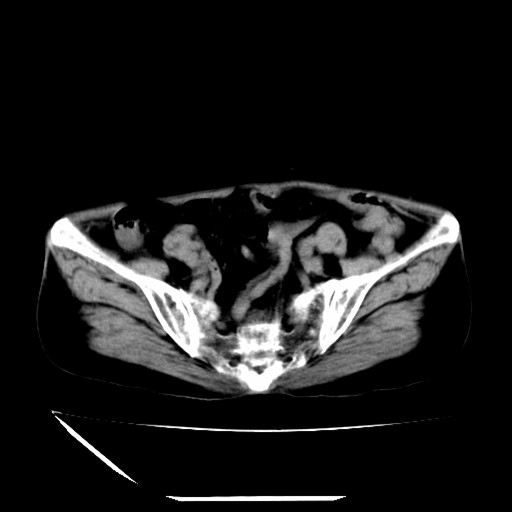

标题: CT16840:女-63岁,下腹部疼痛, [打印本页]

标题: CT16840:女-63岁,下腹部疼痛,

补充资料:血象是13.5,临床拟诊阑尾炎

本人诊断是右肾周围炎,阑尾炎,盆腔少许积液!

我觉得你的诊断欠妥;1)右肾周围炎症?是个什么诊断?2)明显的阑尾炎也没看到,最好不要这样写,就是道格拉斯窝内少量积液。

道格拉斯窝内少量积液。